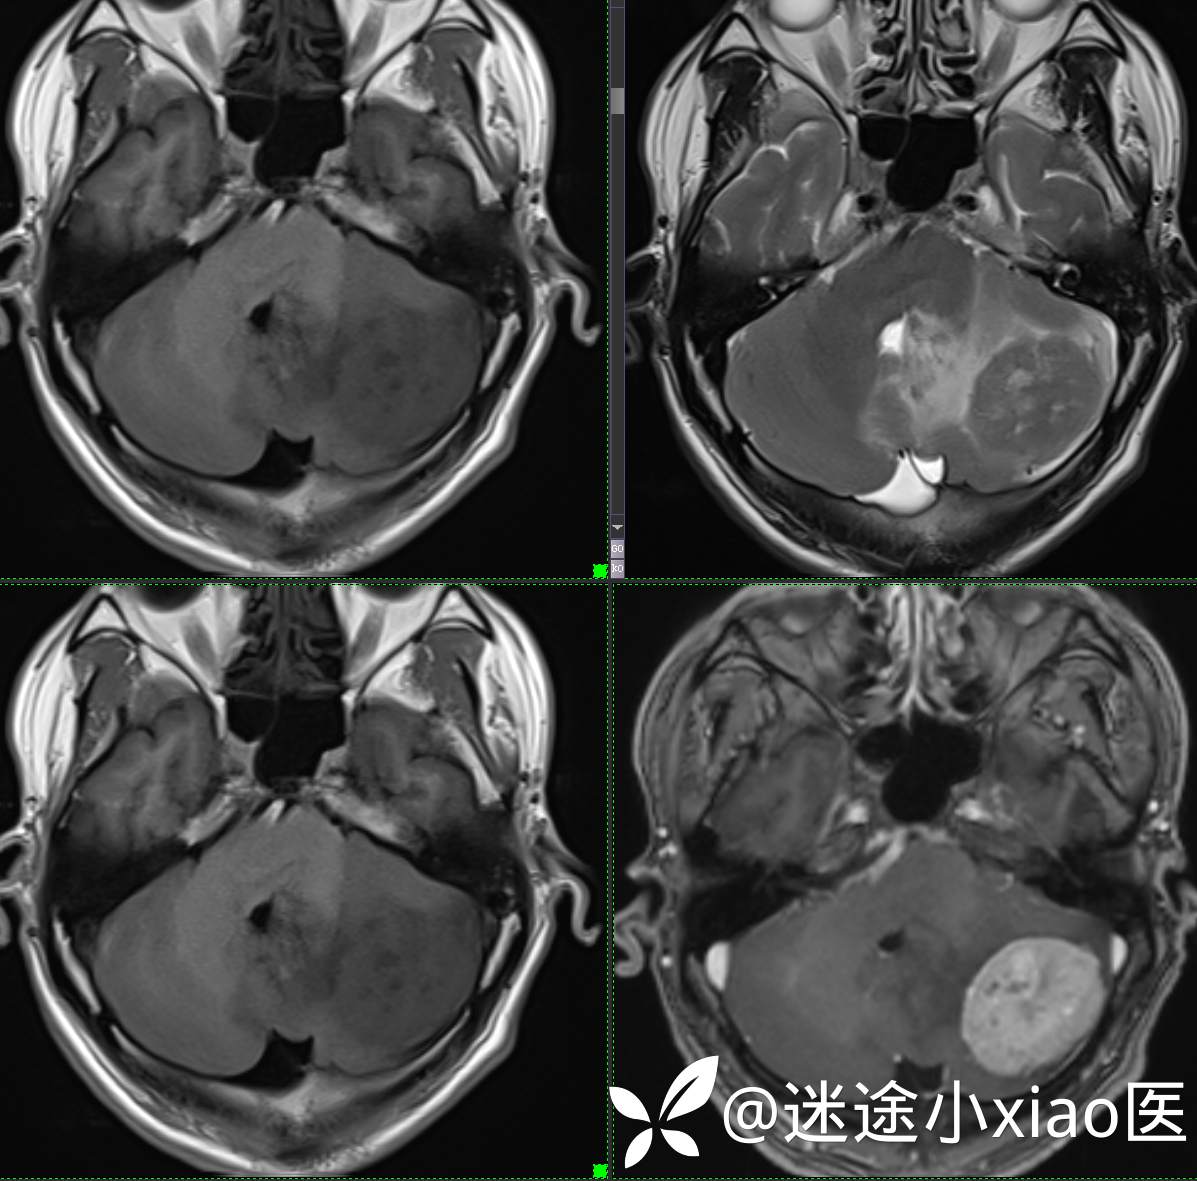

头颈组15:男,62岁,左侧小脑半球占位,原发?转移?是否有意外?

主 诉: 头晕、恶心呕吐半月余。

现病史: 患者半月前无明显诱因下明显头晕,伴恶心呕吐,无意识丧失、无智力明显下降,无视物模糊,无耳鼻腔出血,无四肢抽搐、畸形,无胸闷气促、呼吸困难。

既往:膀胱癌手术史。